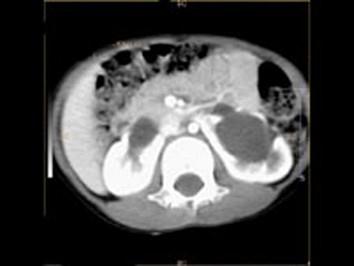

女,6个月,CT扫描如图所示,下列说法错误的是 ( )A、异位肾B、马蹄肾C、双侧肾门朝向前内方D、双肾下极融合E、双侧肾盂积水

问题 女,6个月,CT扫描如图所示,下列说法错误的是 ( )

选项 A、异位肾 B、马蹄肾 C、双侧肾门朝向前内方 D、双肾下极融合 E、双侧肾盂积水

答案 A